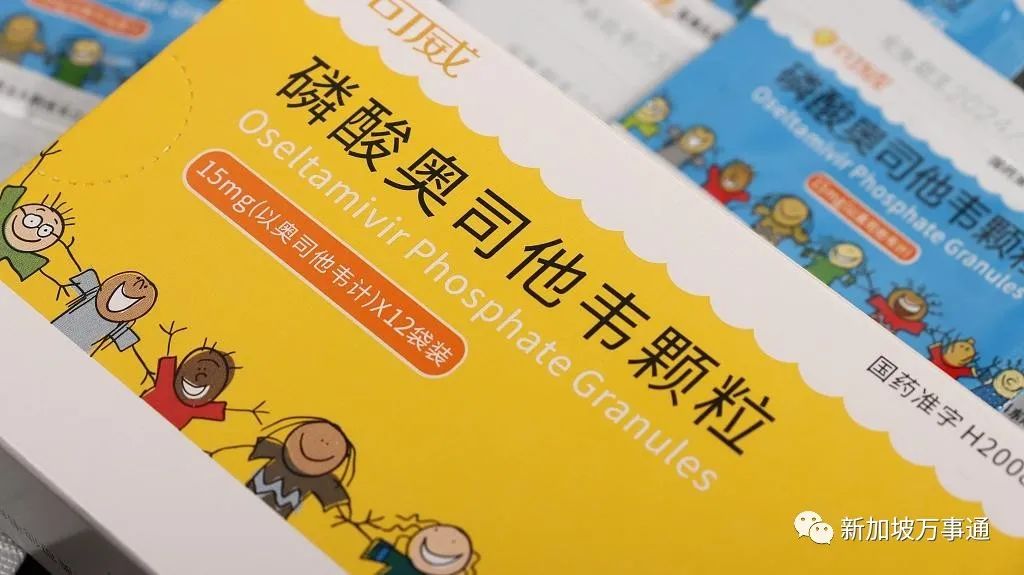

有很多人都有一种感觉,自从新冠一波感染高峰过去后,甲流似乎已经超过新冠,成为当前需要重点提防的病毒了。

大家的感觉并没有错。根据中国疾控中心疫情情况通报,从哨点医院的监测情况看,近3周流感病毒阳性率呈上升趋势,2023年第8周为25.1%,而新冠病毒阳性率则为5.1%。